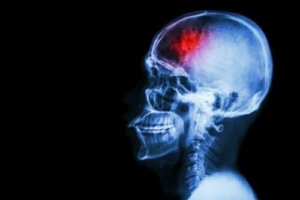

Beynin bir bölgesine giden kan akışı yetersiz kaldığında ya da kesildiğinde bir felç meydana gelir. Sonuç olarak, nöronlar hasar görebilir ve hatta ölebilir. Bundan kaçınmak için, işte felci önleyici bazı tedbirler.

Felç, beyne kan sağlayan kan damarlarını etkileyen serebrovasküler bir hastalıktır. Bir kan damarı kırıldığında ya da bir pıhtı veya başka bir parçacık tarafından tıkandığında felç meydana gelir.

Bir MSD Kılavuzu makalesinin ayrıntılandırdığına göre, bu kırılma ya da tıkanma nedeniyle, beynin bir kısmı ihtiyaç duyduğu kan, oksijen ve glikoz akışını alamaz. Sonuç, etkilenen beyin bölgesindeki sinir hücrelerinin oksijen almamasıdır. Böylece işlevlerini yerine getiremezler ve birkaç dakika içinde ölürler.